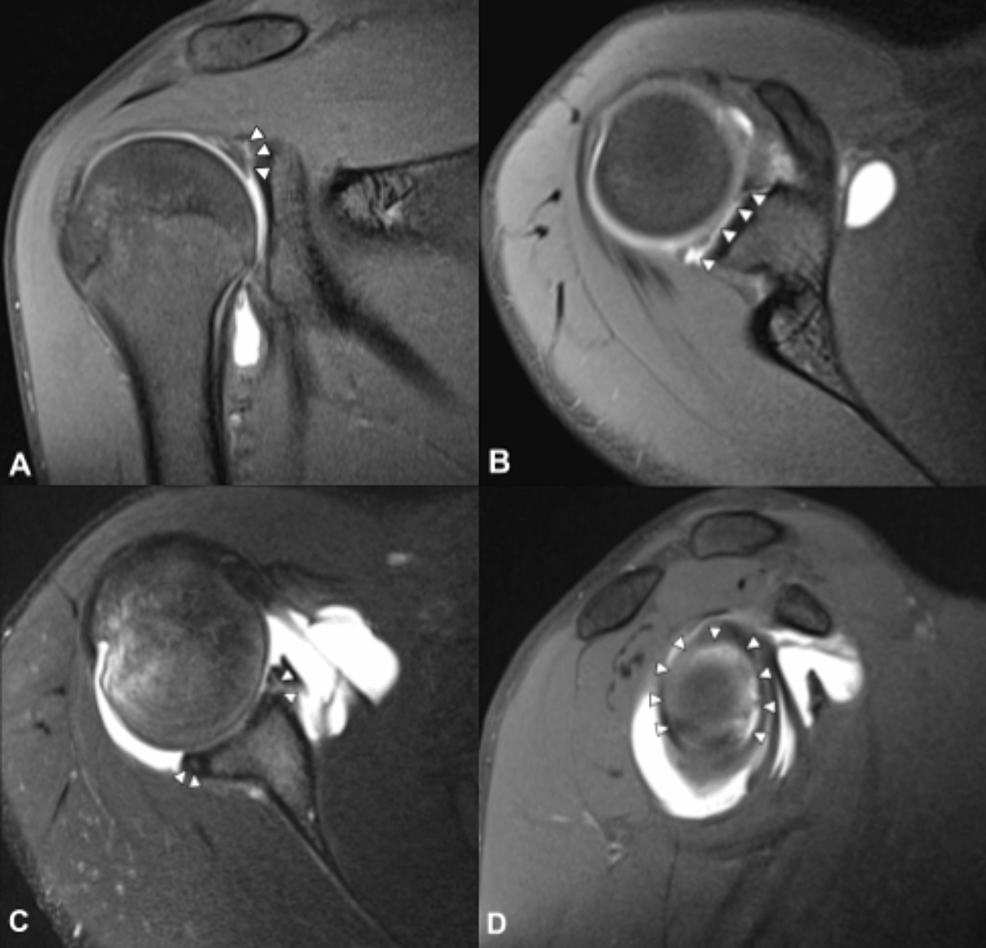

From www.ajronline.org

Increased Risk of Posterior Glenoid Labrum Tears in Football Players AJR Throwing A Football After Labrum Surgery However, with proper treatment and rehabilitation, returning to sports and activities is possible. It helps to cushion and stabilize the joint, but when. Patients may be able to return to sports six months to one year after surgery. Suffering a labral tear can be a setback for athletes and active individuals. One of the most common injuries sustained by throwing. Throwing A Football After Labrum Surgery.

From www.researchgate.net

A 22yearold male collegiate football player with a right posterior Throwing A Football After Labrum Surgery Suffering a labral tear can be a setback for athletes and active individuals. In addition to eliminating pain and inflammation, the rehabilitation process for throwing athletes must include the restoration of motion, strength, and endurance, as well as restoration of proprioception, dynamic stability, and neuromuscular control. Slap repairs, once the standard surgical approach, involve reattaching the torn labrum to the. Throwing A Football After Labrum Surgery.